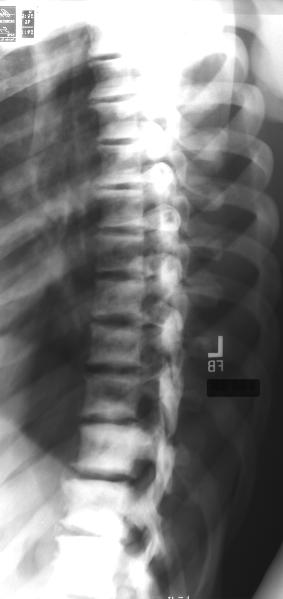

osteopetrosis2.jpg (14997 bytes)osteopetrosis4.jpg (20981 bytes)

After reviewing the above x-rays of this 40 year old male, the best diagnosis is:

Osteopetrosis